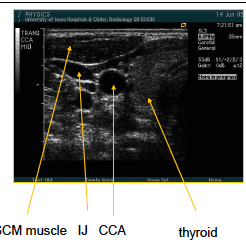

what are teh arrows pointing to here? what image is being taken?

trans CCA mid